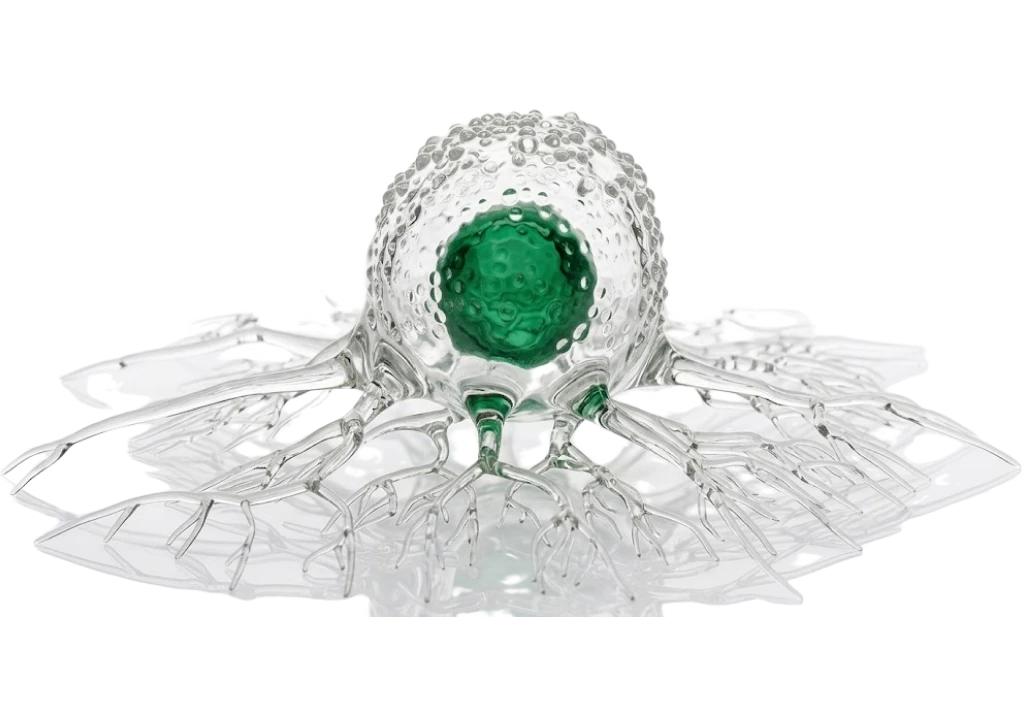

Онкология